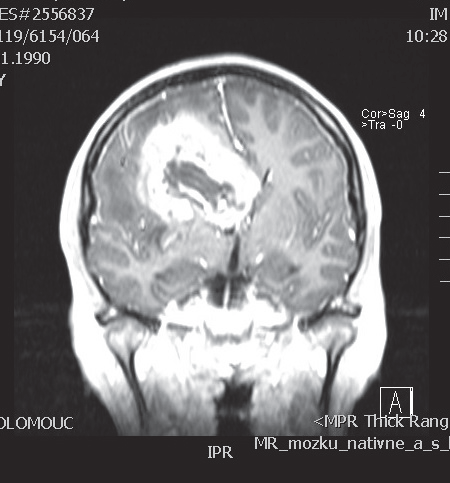

V naší kazuistice prezentujeme 25letou pacientku s negativní onkologickou rodinnou anamnézou, která dosud vážněji nestonala. Udávala asi 3 měsíce progredující bolesti hlavy a krční páteře, zvracení, postupně rozmazané vidění a parestezie horních končetin. Byla provedena magnetická rezonance, na které diagnostikován tumor mozku ve frontálním laloku vpravo, vyplňující frontální roh postranní komory velikosti 6x5 cm, midline shift, mass efekt. Dne 23. 9. 2013 ji byla na neurochirurgické klinice provedena neradikální exstirpace tumoru z parasagitální kraniotomie. Histologicky byl prokázán glioblastom multiforme gr. IV. Od 30. 10. 2013 do 12. 12. 2013 absolvovala konkomitantní radiochemoterapii (radioterapie do CLD 60,0 Gy) s temozolomidem (75 mg/m2 per os D1-42). Od ledna do dubna 2014 pokračovala v chemoterapii temozolomid solo v dávce 150 mg/m2, resp. od 2. cyklu 200 mg/m2 D1-5 ( Temodal tbl, celkem 4x). Na kontrolní MRI mozku ze dne 20. 5. 2014 byla prokázána progrese rezidua. Dne 4. 6. 2014 podstoupila druhou operaci, histologicky verifikován glioblastom multiforme s přechodem v gliosarkom. Snažili jsme se získat informace ze zahraniční literatury s léčbou gliosarkomu, bohužel se jedná o velmi vzácné onemocnění a údajů není mnoho. Nakonec byla zvolena léčba podle protokolu ICE (ifosfamid, carboplatina, etoposid), který je obdobou režimu PEI. Dávky: ifosfamid 1000 mg/m2 D1-3, carboplatina 110 mg/m2 D1 a etoposid 100 mg/m2 D1-3 v pětitýdenním cyklu. Pacientka zahájila 1. sérii od 1.7.2014 s podporou G-CSF (Neulasta s.c.). Léčbu tolerovala dobře, bez akutních či pozdních vedlejších nežádoucích účinků a významné hematologické toxicity. Po 3 cyklech podstoupila kontrolní MRI, kde popsána parciální regrese periferního sycení – rezidua tumoru. Po dalších 3 cyklech chemoterapie provedena restagingová MRI, kde popsána opět mírná regrese rezidua tumoru. Celkový stav pacientky se během léčby postupně zlepšoval, je mobilní, bez psychoorganického syndromu. Byly vysazeny kortikoidy, což vedlo k ústupu cushingoidního syndromu. Bylo rozhodnuto o pokračování v dalších 2 cyklech udržovací chemoterapie, na kontrolní MRI ze 14. 4. 2015 a 7. 7. 2015 popsána stabilizace onemocnění.